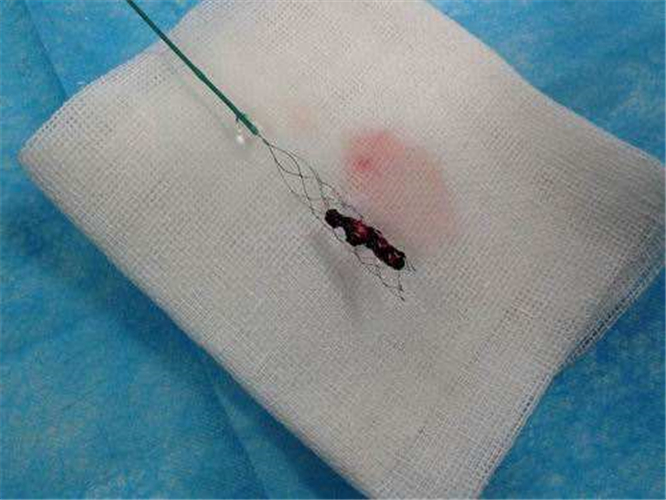

支架取出的腦梗塞血栓